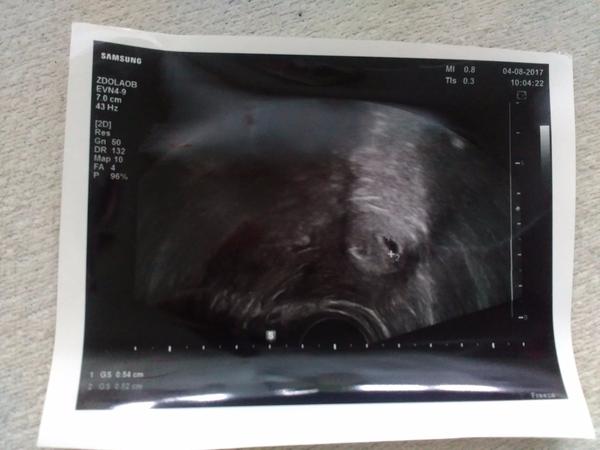

Ahoj holky, nesu slíbené zprávy 🙂 dnešní test z moči po týdnu od minulého je 100x lépe vidět. A z krve 28.7. bylo HCG 163,6 a dnes bylo 3310. Takže vše dobře prospívá. Dokonce už byla na ultrazvuku vidět i malička fazolka... Už se nemůžu dočkat další kontroly. Doktor z car mně odeslal zpátky k obvodní gynekoložce. Takzr snad se vše vydaří a bude to dobré.. 🙂❤ co říkáte?? 🙂